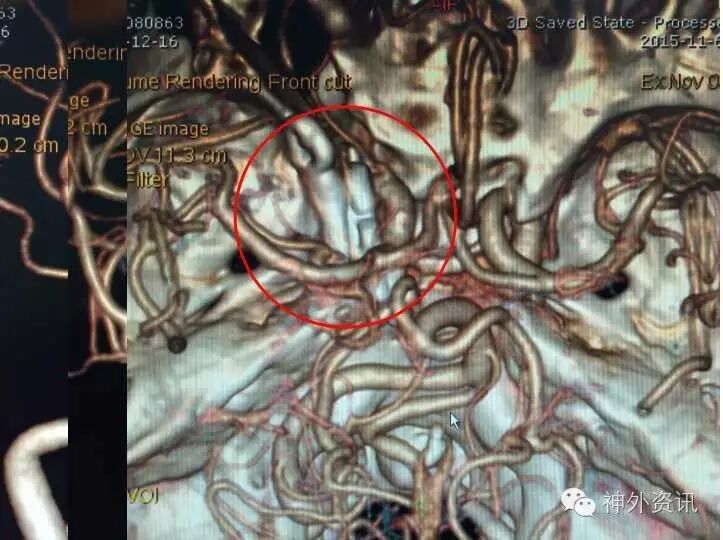

《床突上段大动脉瘤》